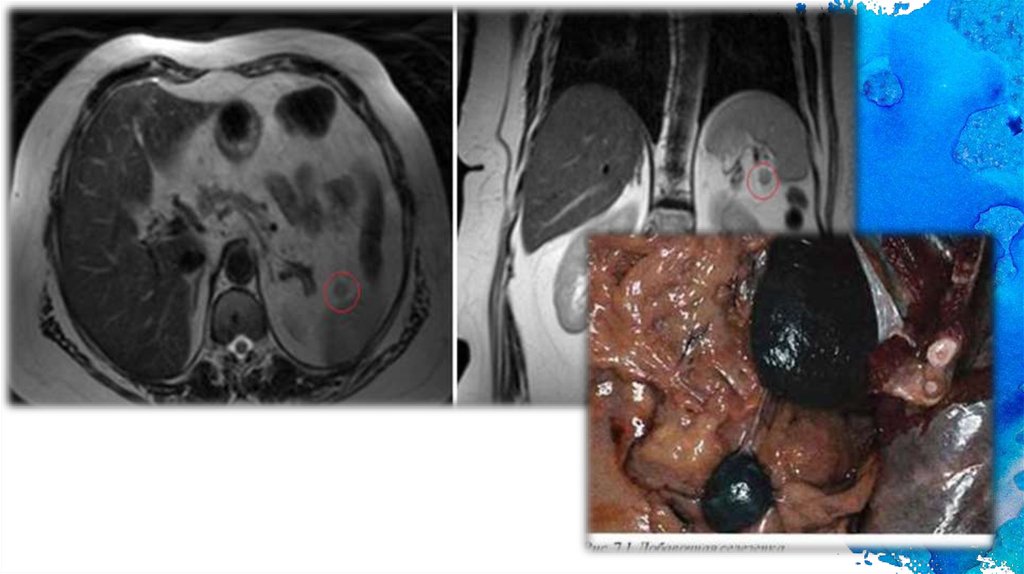

Пороки развития

1. Добавочные дольки селезенки

2. двойная селезенка – два обращенных друг к другу

воротами органа почти одинаковой величины и формы.